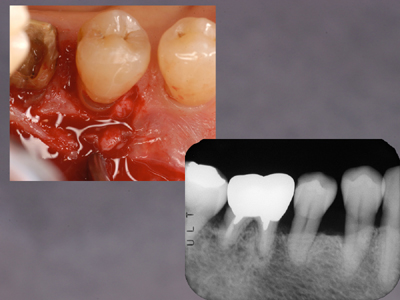

さて宿題の症例にもどって、13年後の解答です。

レントゲン上でもリエントリーでの肉眼所見でも骨欠損は認められませんし、ふたつの実験結果からの反証とも異なると思います。

今回の症例では咬合調整は一切行っていません。ルートプレーニングのみによる大きな治癒の可能性を再確認しました。プロービングデプス、デンタル上での骨欠損とその変化、歯周病の治癒の様式etc.いくつものテーマが示唆されると思います。いずれも「剱Basic」として繰り返し学んでいることです。